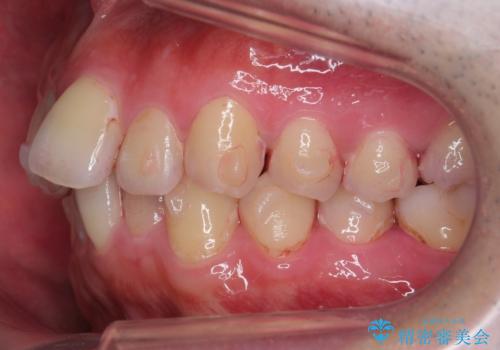

出っ歯と歯のねじれ 非抜歯で 30代男性

右の歯並びが1本分上が前にずれていました。

今回は右のかみ合わせはそのままにしました。左は特に初めから問題ない状態でした。